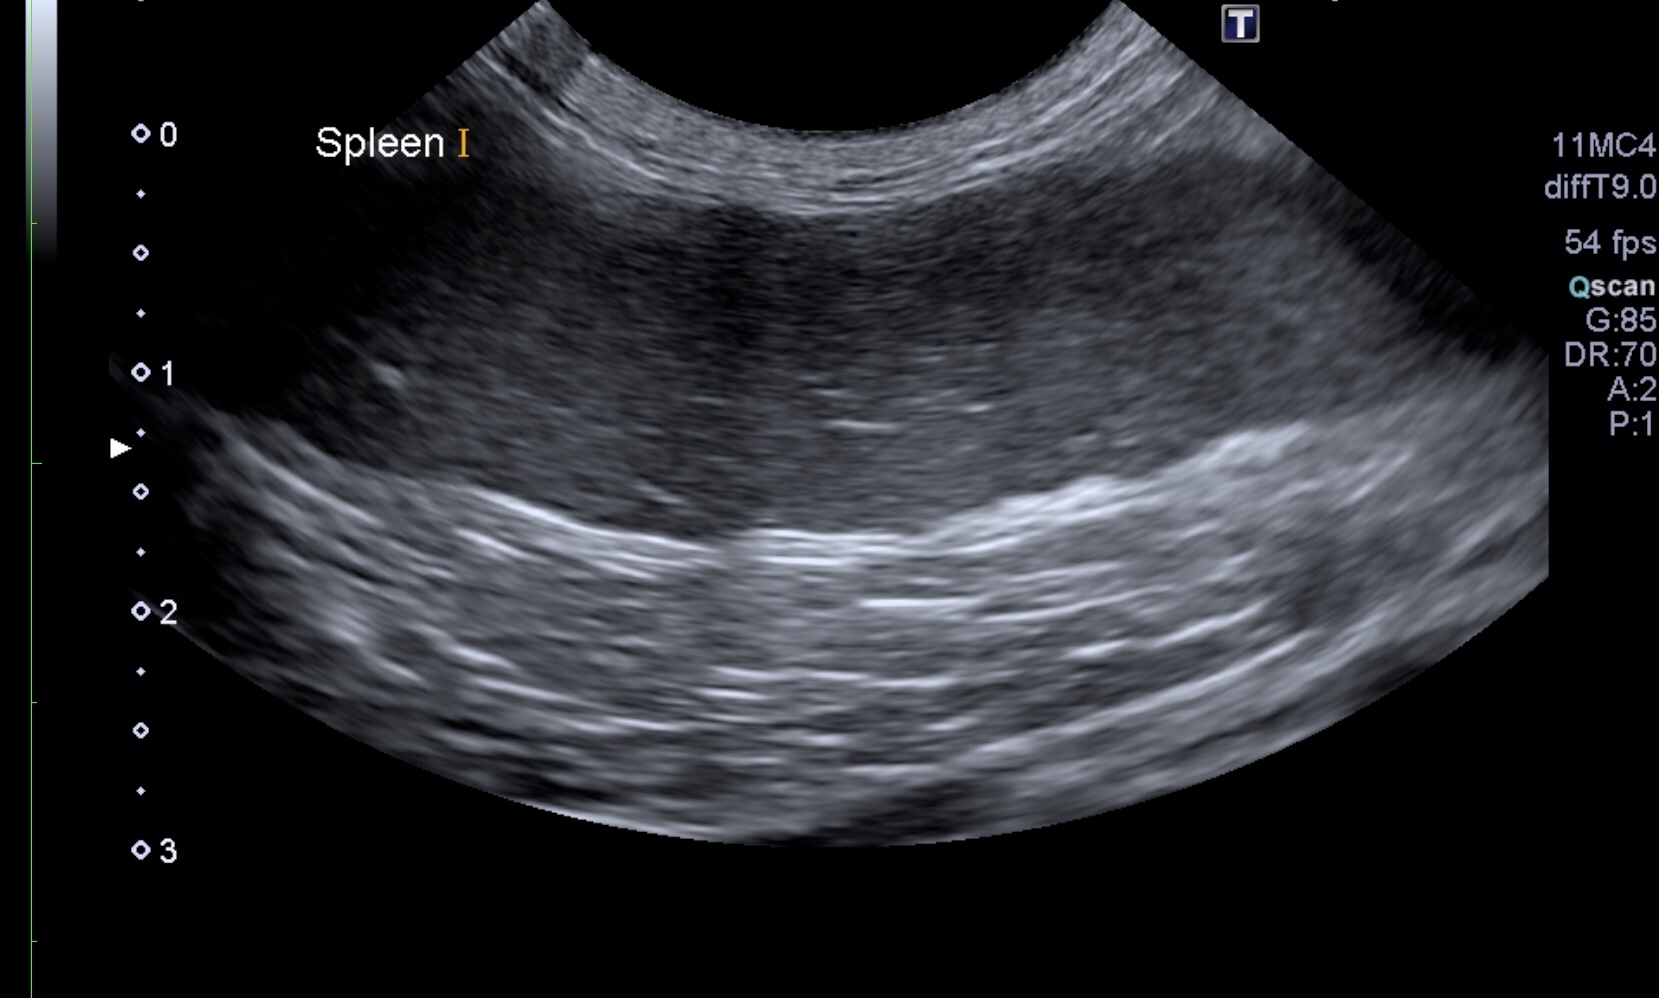

血液検査や超音波検査を実施したところ、内臓(脾臓)や血液中にも腫瘍細胞の浸潤が疑われました。(写真2)(写真3)

写真2:脾臓の超音波画像